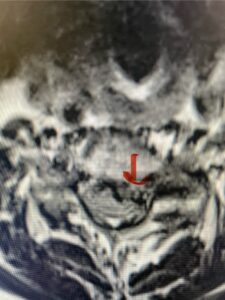

Another patient, a 77 year-old female, presents with pain, numbness, and weakness of her arms and difficulty with balance over a 6-month period. MRI revealed severe osteophytic disease at C5-C7 with cord compression (Fig. 4). Further work-up by fine-cut cervical CT to evaluate the nature of compression revealed a completely calcified osteophyte (Fig. 5). Although the patient had a good lordosis and a posterior cervical approach would accomplish an adequate decompression, we elected to perform a two-level anterior cervical discectomy and fusion. This particular osteophyte is formidable because of its size but the compression was all anterior and would be a less invasive approach. Fortunately, during the procedure, the patient had a fair amount of osteoporosis which allowed the osteophyte to be drilled and bit away with considerable ease. Interestingly, the C6 7 osteophyte which was more a sheet of osteophyte was more challenging to remove. In the end the decompression went well, and we placed two interbody devices filled with bone graft with plates at each level (Fig. 6). The patient had a nice recovery with immediate reduction of pain and numbness. This case demonstrates the importance of recognition of cervical myelopathy in its early stages. A significant reversal of function is generally the rule if the patient has appropriate correlative findings on exam and MRI, particularly with long tract distribution weakness development within a year time period.

Fig 5a: Sagittal and axial cervical fine-cut CT scan demonstrating severe osteophyte formation causing cord compression at C 56 (red arrow)

Fig 5b: Sagittal and axial cervical fine-cut CT scan demonstrating severe osteophyte formation causing cord compression at C 56 (red arrow)